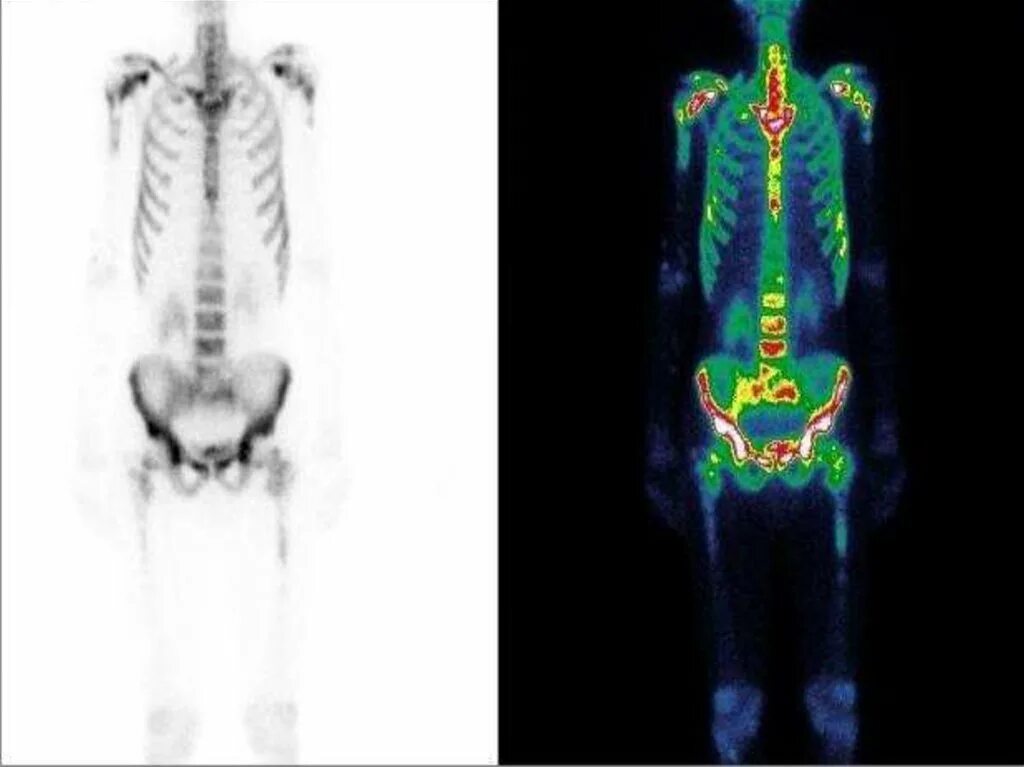

Метастазы скелета